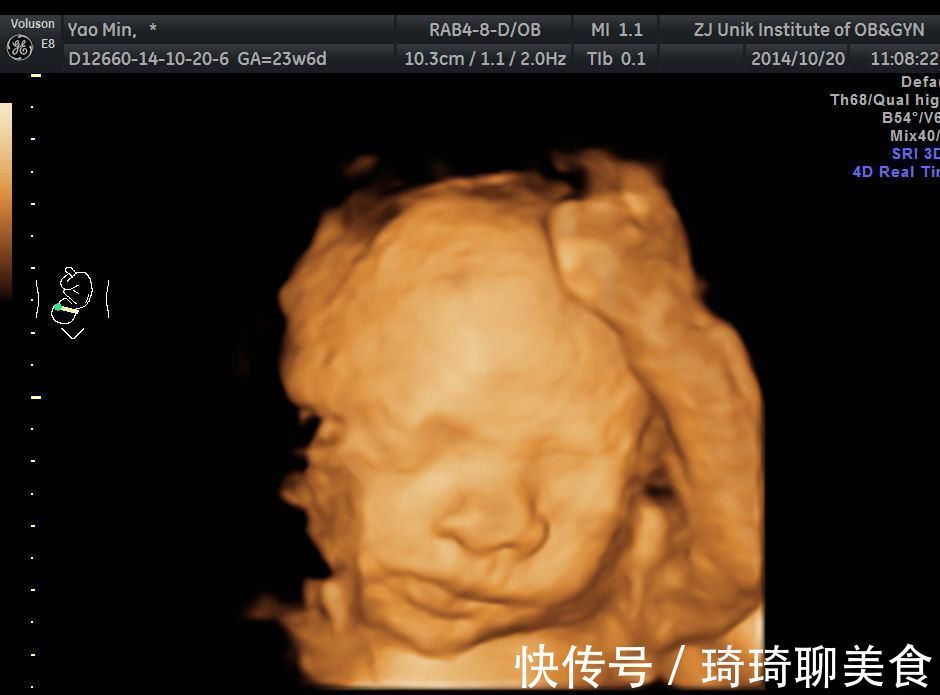

孕妇|孕妇做四维彩超,胎儿鼻子扁又大,胎儿也是有苦说不出啊!

有孕妈去做了四维彩超,拿到了一张宝宝的照片,开始是很惊喜的,结果随后一看,有点吃惊。为什么鼻子那么突出、那么大,趴在脸上,好难看啊!摸摸自己的鼻子,再去镜子前面照一照,也没有多大,大小适中,很匀称,宝宝这个就不太成比例。难道宝宝没有遗传自己的鼻子,以后会不会变得很丑呢?

四维彩超鼻子大、四维彩超长相很丑,这些事都不需要纠结,因为四维彩超呈现的图像根本就不是太儿真实的样子,只是非常逼真而已,所以不要太在意。四维彩超的目的是能更清晰地辨别胎儿畸形,现在被很多朋友用来留作胎儿纪念,也作为医院提高收入的一种手段,实际上是有些走偏了。

四维彩超宝宝鼻子大,是怎么回事?

四维彩超为什么鼻子大呢?一般有下面几种原因。

相对来说大一些

做四维彩超时,胎儿还非常小,总体长度约30厘米,头部的长度大约是15厘米,胎儿还非常瘦小,基本上是皮包骨头,面部只有鼻子是突出的,其他都是下凹或者平面状态,所以鼻子显得格外突出,相对来说比较大。等出生后,面部肌肉越来越饱满,眼睛变大了,鼻子的大小也会更加对称了。

成像原理导致的

四维成像的远离不是小孔成像,不是拍的时机照片,而是在二维基础上,加上时间维度,用电脑软件合成的图像。四维彩超会将立体模式进行重建,将胎儿的面部结构更为清晰、更为直观地显示出来,有利于将可靠的依据提供给胎儿面部畸形筛查。

胎儿体位导致的

胎儿做四维彩超的时候,一般不会直接将正脸对着我们,我们看到的多是侧面图像,但是为了更清晰的判断鼻子、嘴唇等面部的结构,会尽量合成一个正面的图像,合成过程中出现了失真的情况,导致鼻子比实际要大。

胎儿受到挤压

胎儿在子宫内的时候,空间有限,还受到羊水的压力,鼻子实际上是有些扁平的,就是一种塌鼻子的状态,出生之后,没有这个压力,会逐渐变得舒展,鼻子就会开始呈现他本来的样子,逐渐挺拔,该高就高,该尖就尖。

胎儿本身鼻子大

如果胎儿本身的鼻子非常大,照出来以后自然也不会太小了,可以看一下爸爸妈妈的鼻子,是不是比较大,如果本身也不小的话,就是遗传起作用,完全不用担心了。如果自己的鼻子不大,可能是上面这些原因造成的,不要给自己造成太多困扰。

总之,四维彩超宝宝鼻子偏大也是正常现象,只要胎儿的鼻子结构没有问题,就大可放心,毕竟,做四维彩超主要目的是排除畸形,不是为了给宝宝拍一张修饰好的美颜照片。您说呢?